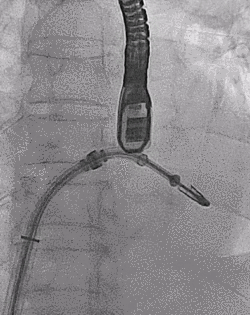

患者全麻以后,在经食道超声心动图和X射线引导下,经股静脉入路,将MitraClip瓣膜夹顺利送至二尖瓣前后叶交界中心处,成功捕捉二尖瓣前叶A2和后叶P2,经超声心动图反复确认瓣叶夹持牢固后,测定有效夹持长度10.4mm,评估反流量降至轻度,释放瓣膜夹,超声心动图评估瓣膜夹位置和功能良好,测定左房压降至26/12mmHg,再次评估反流量仍为轻度,手术顺利完成。

▲ MitraClip释放

王焱、王斌教授团队通过术前和台北荣民总医院(Taipei Veterans General Hospital)宋思贤教授进行了详细的讨论并制定了最优的手术策略,同时术中视频连线获得宋思贤教授的技术支持,华体会体育官方网站 超声内科苏茂龙教授负责术中超声心动图引导。患者全麻以后,在经食道超声心动图和X射线引导下,经股静脉入路,将MitraClip瓣膜夹顺利送至二尖瓣前后叶交界中心处,成功捕捉二尖瓣前叶A2和后叶P2,经超声心动图反复确认瓣叶夹持牢固后,测定有效夹持长度11mm,评估反流量降至微量,释放瓣膜夹,超声心动图评估瓣膜夹位置和功能良好,测定左房压降至11/6mmHg,再次评估反流量仍为微量,手术顺利完成。